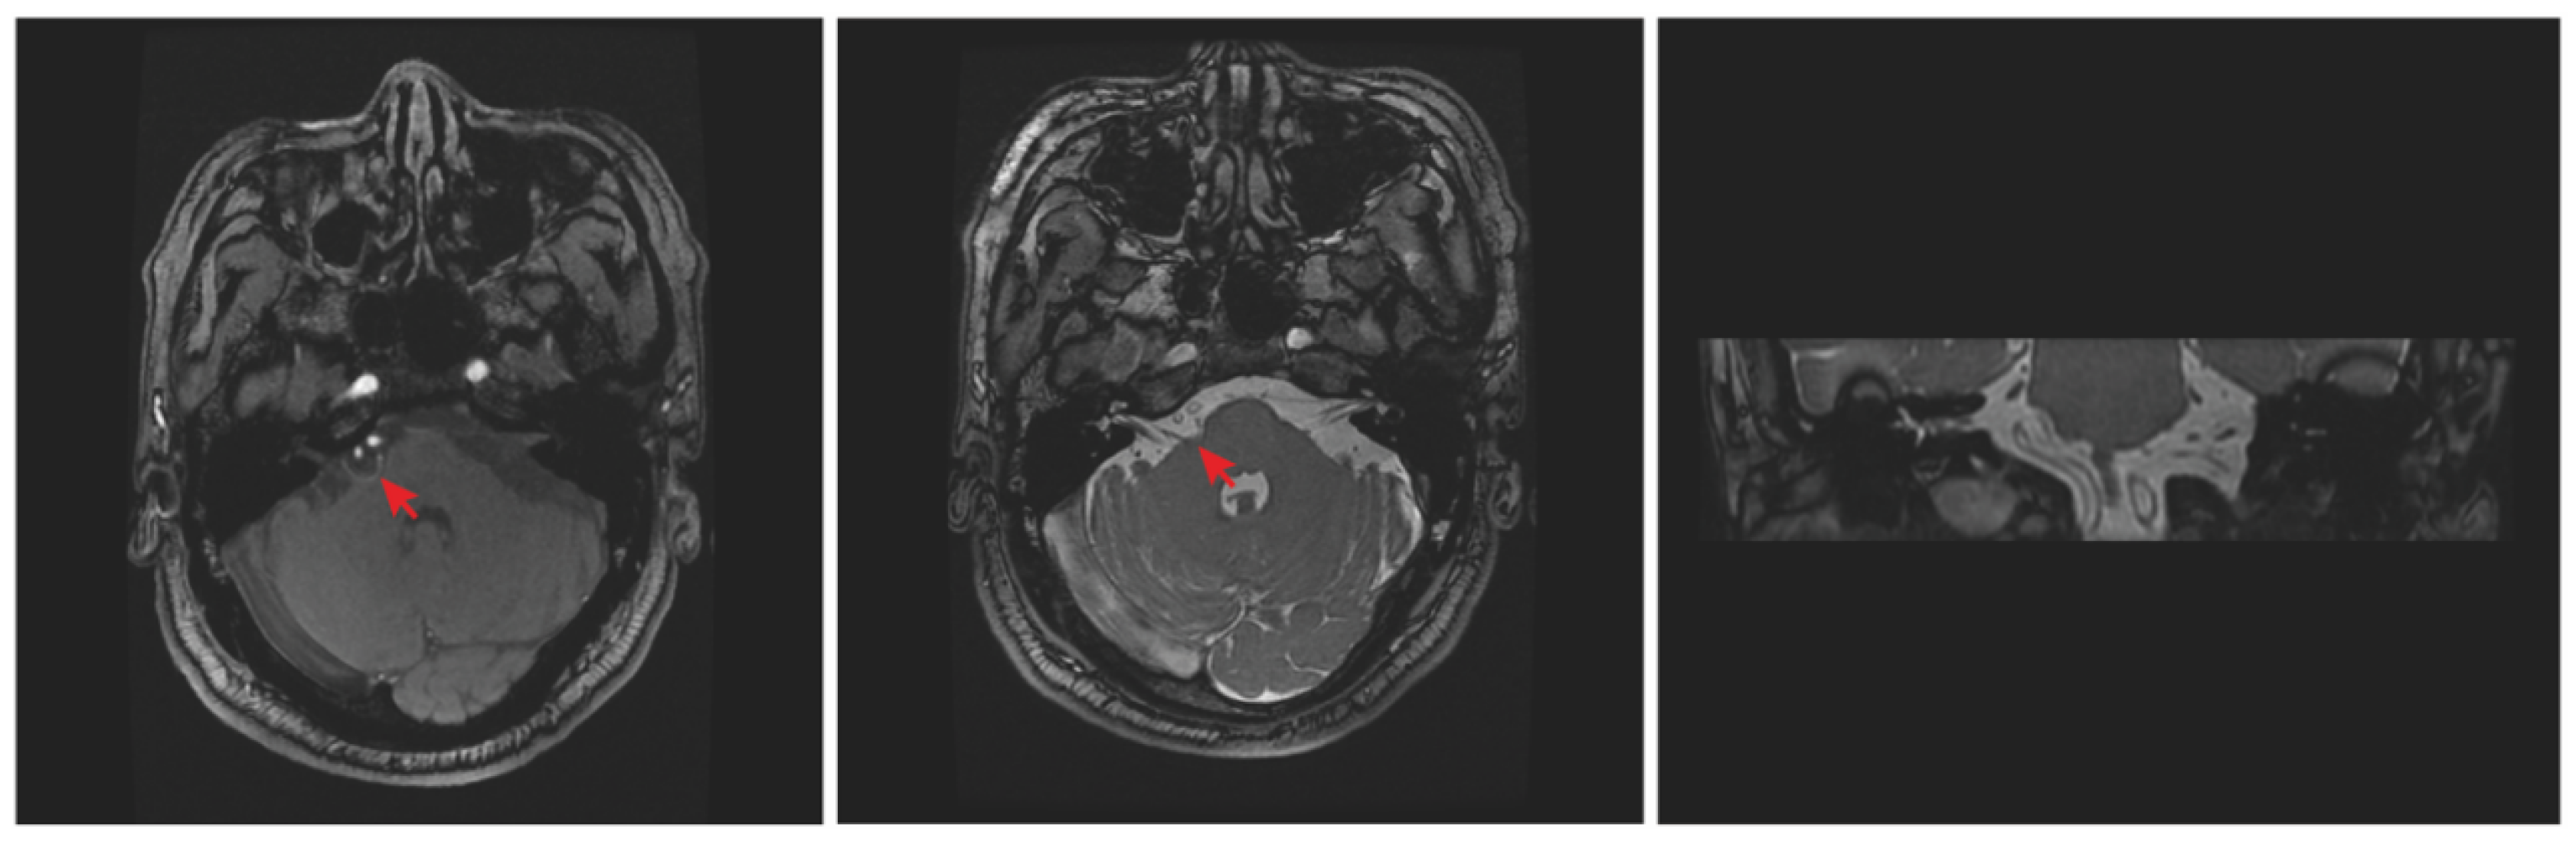

2. Case Report